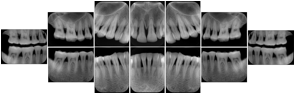

6 Standard + 4 Bitewing C Dental Image Layout

DL-P002E

Reference:

01

Standard

11, 12, 21, 22

11

32, 31, 41, 42

20

Bitewing

18, 17, 16, 15, 48, 47, 46, 45

21

17, 16, 15, 14 47, 46, 45, 44

23

27, 26, 25, 24, 37, 36, 35, 34

24

28, 27, 26, 25, 38, 37, 36, 35